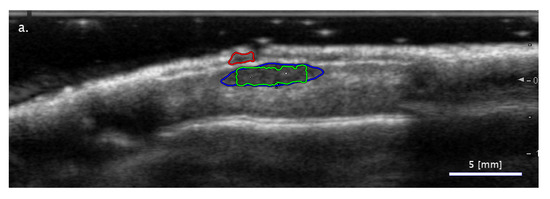

3.2.1. Cases When FA Fails While SA Methods Perform Correctly

3.2.2. Cases When the Two SA Methods Return Different Classifications